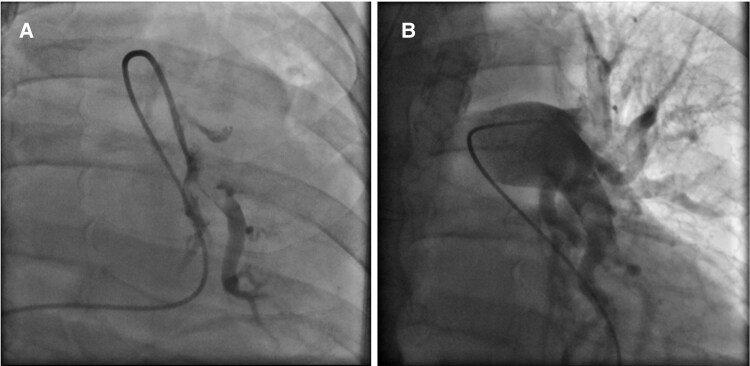

Case summary: A 73-year-old White male was hospitalized in order to perform abdominal surgery. Afterwards, multiple complications led to recurring operations and a prolonged immobilization time. In the aftermath, the patient suffered an in-hospital cardiac arrest and was put on VA-ECMO. A computed tomography pulmonary angiography presented bilateral central PE. Due to contraindications for systemic thrombolysis, successful CDT using a FlowTriever catheter was performed, leading to a reduction of mean pulmonary arterial pressure. ECMO therapy could be terminated in the following days. The patient was eventually discharged without any signs of right heart strain in transthoracic echocardiogram, neurological sequelae or dyspnoea.